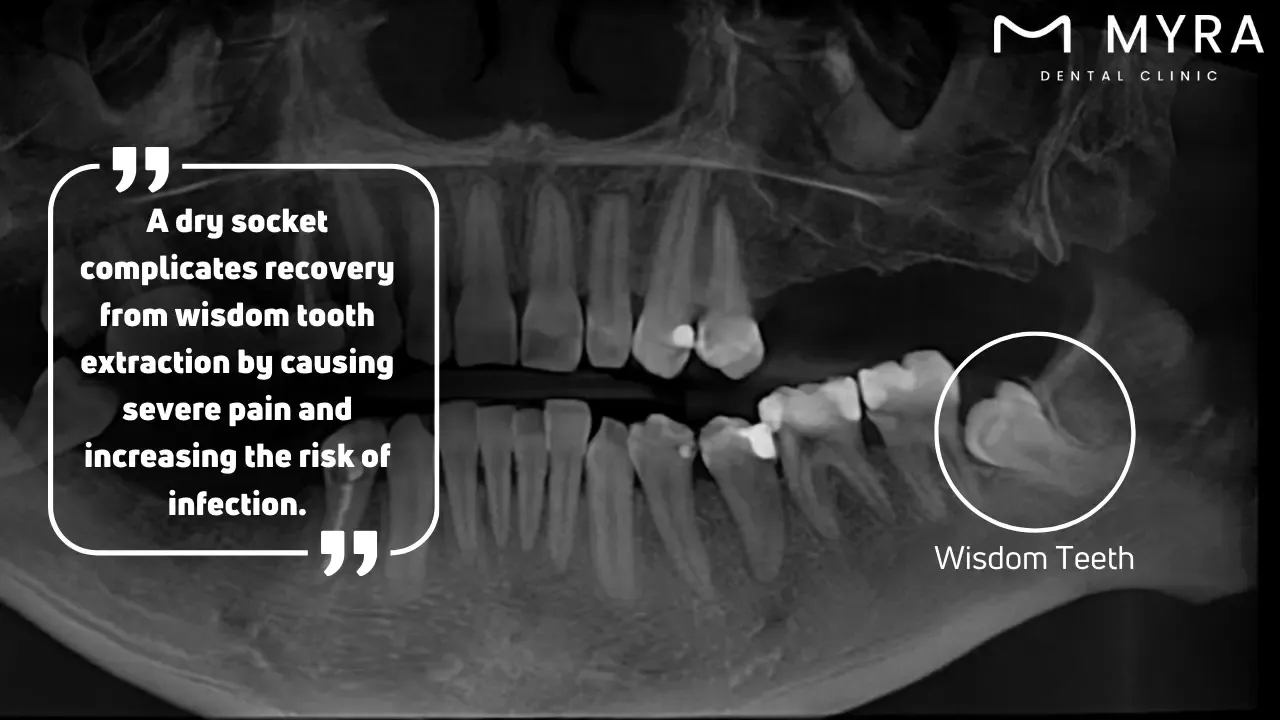

How do Dry Socket Affect Wisdom Tooth?

A dry socket affects a wisdom tooth by inducing excruciating pain and complications that impede post-extraction recovery. A hemostatic clot usually forms at the wisdom teeth extraction site to protect the surrounding nerves and osseous tissues. The clot either dislodges or does not grow enough, exposing the bone and neural tissues in a dry socket. The exposure precipitates intense pain that radiates to the auricular, ocular, or cervical regions on the same side as the extraction, making it a particularly aggravating problem with wisdom tooth extractions.

Dry socket wisdom teeth present unique challenges due to the anatomical positioning and complexity of extracting third molars. Wisdom teeth, the terminal set of molars, are more arduous to extract, elevating the risk of dry socket development. The difficulty in sustaining optimal oral hygiene in the posterior region of the oral cavity and the propensity for food particles and bacteria to lodge in the extraction site further exacerbate the situation. The condition intensifies the pain and extends the convalescence period, rendering dry socket wisdom teeth an incredibly protracted and painful ordeal.

The problem with wisdom tooth dry socket is not confined solely to pain; it augments the risk of infection. The exposed osseous structures and nerves are susceptible to bacterial colonisation, heightening the risk of infection. It manifests as swelling, pyrexia, and additional discomfort, further complicating the recovery.